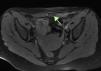

A 32-year-old woman on follow-up in gastroenterology outpatients for ileocolic Crohn disease had started to experience cyclic abdominal pain, with appearance of a mass close to the scar resulting from a cesarean section performed 10 years previously. Abdominal ultrasound showed a 4.7cm×3cm solid lesion inside the right anterior rectus abdominis muscle, hypoechoic with respect to the muscle and with no flow on colour Doppler imaging, in addition to 3 cystic lesions on its periphery (Figs. 1 and 2). All findings were suggestive of endometrioma. Magnetic resonance imaging (MRI) requested for better characterisation showed the lesion to be T1-hypointense relative to surrounding muscle, containing hyperintense foci on fat-suppressed T1-weighted images, suggestive of haemorrhagic foci (Figs. 3 and 4). Ultrasound-guided fine needle aspiration (FNA) found cytology consistent with endometriosis. As the patient was asymptomatic and did not wish to undergo surgery, it was initially decided to monitor the lesion by ultrasound. She is currently receiving only analgesic treatment on demand, with which she controls the cyclic episodes of abdominal pain. The lesion has remained stable in the follow-up ultrasounds, and comparable to the size at diagnosis.

Endometriomas of the anterior abdominal wall are chiefly diagnosed by ultrasound or MRI.6 Their ultrasound characteristics are a hypoechoic, heterogeneous mass, with internal echoes, more rarely solid or even with cystic changes (pools of blood secondary to a recent bleed). They are usually accompanied by a hyperechoic halo due to inflammation of the surrounding tissue.4,5 Colour Doppler shows a vascular pedicle at the periphery, with low intralesional signal intensity.7 The lesion appears as a solid mass on computed tomography (CT), isodense relative to muscle, while on MRI it appears as isointense to muscle on T1-weighted images and as high signal intensity on T2-weighted images, both with contrast uptake in the arterial phase.5 All these features are very non-specific for making a correct preoperative diagnosis, which is only achieved in 20–50% of cases,4,5,7 probably due to low clinical suspicion due to the non-specific nature of the symptoms, and their late development (between 2 and 5 years after the surgery).2,3,5,7 Ultrasound-guided FNA is the first approach to determine the nature of the lesion. It is limited by the scant cellularity in cystic or bleeding lesions, which is insufficient for a correct histological diagnosis, as well as the frequent atypia of the glandular cells, which makes differential diagnosis difficult. The presence of 2 of the 3 typical components (endometrial glandular cells, stromal cells or macrophages with haemosiderin) confirms the diagnosis of endometriosis by FNA.8,9 Its use is still not clear due to the risk of creating new implants.4 CA-125 determination is not recommended owing to its low sensitivity.1,7